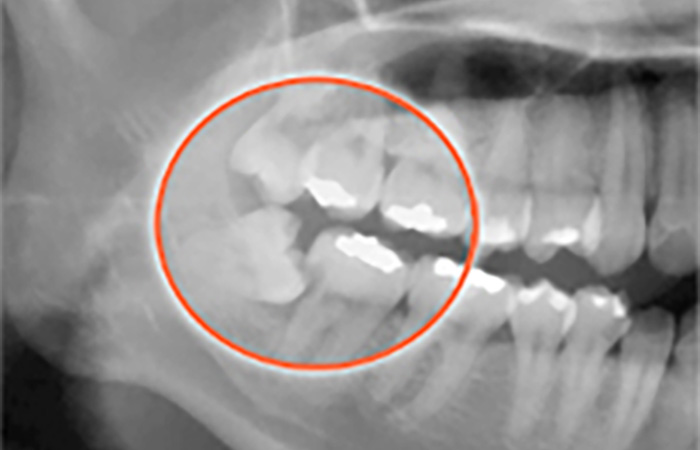

「親知らずの状態がわからない」という方も、レントゲンを撮って確認しましょう。

親知らず抜歯の難易度

親知らずの抜歯は、親知らずの生え方によって難易度が異なります。歯ぐきに埋まっている、斜めや横に生えている親知らずは、手術の難易度が高く負担が大きくなる傾向にあります。